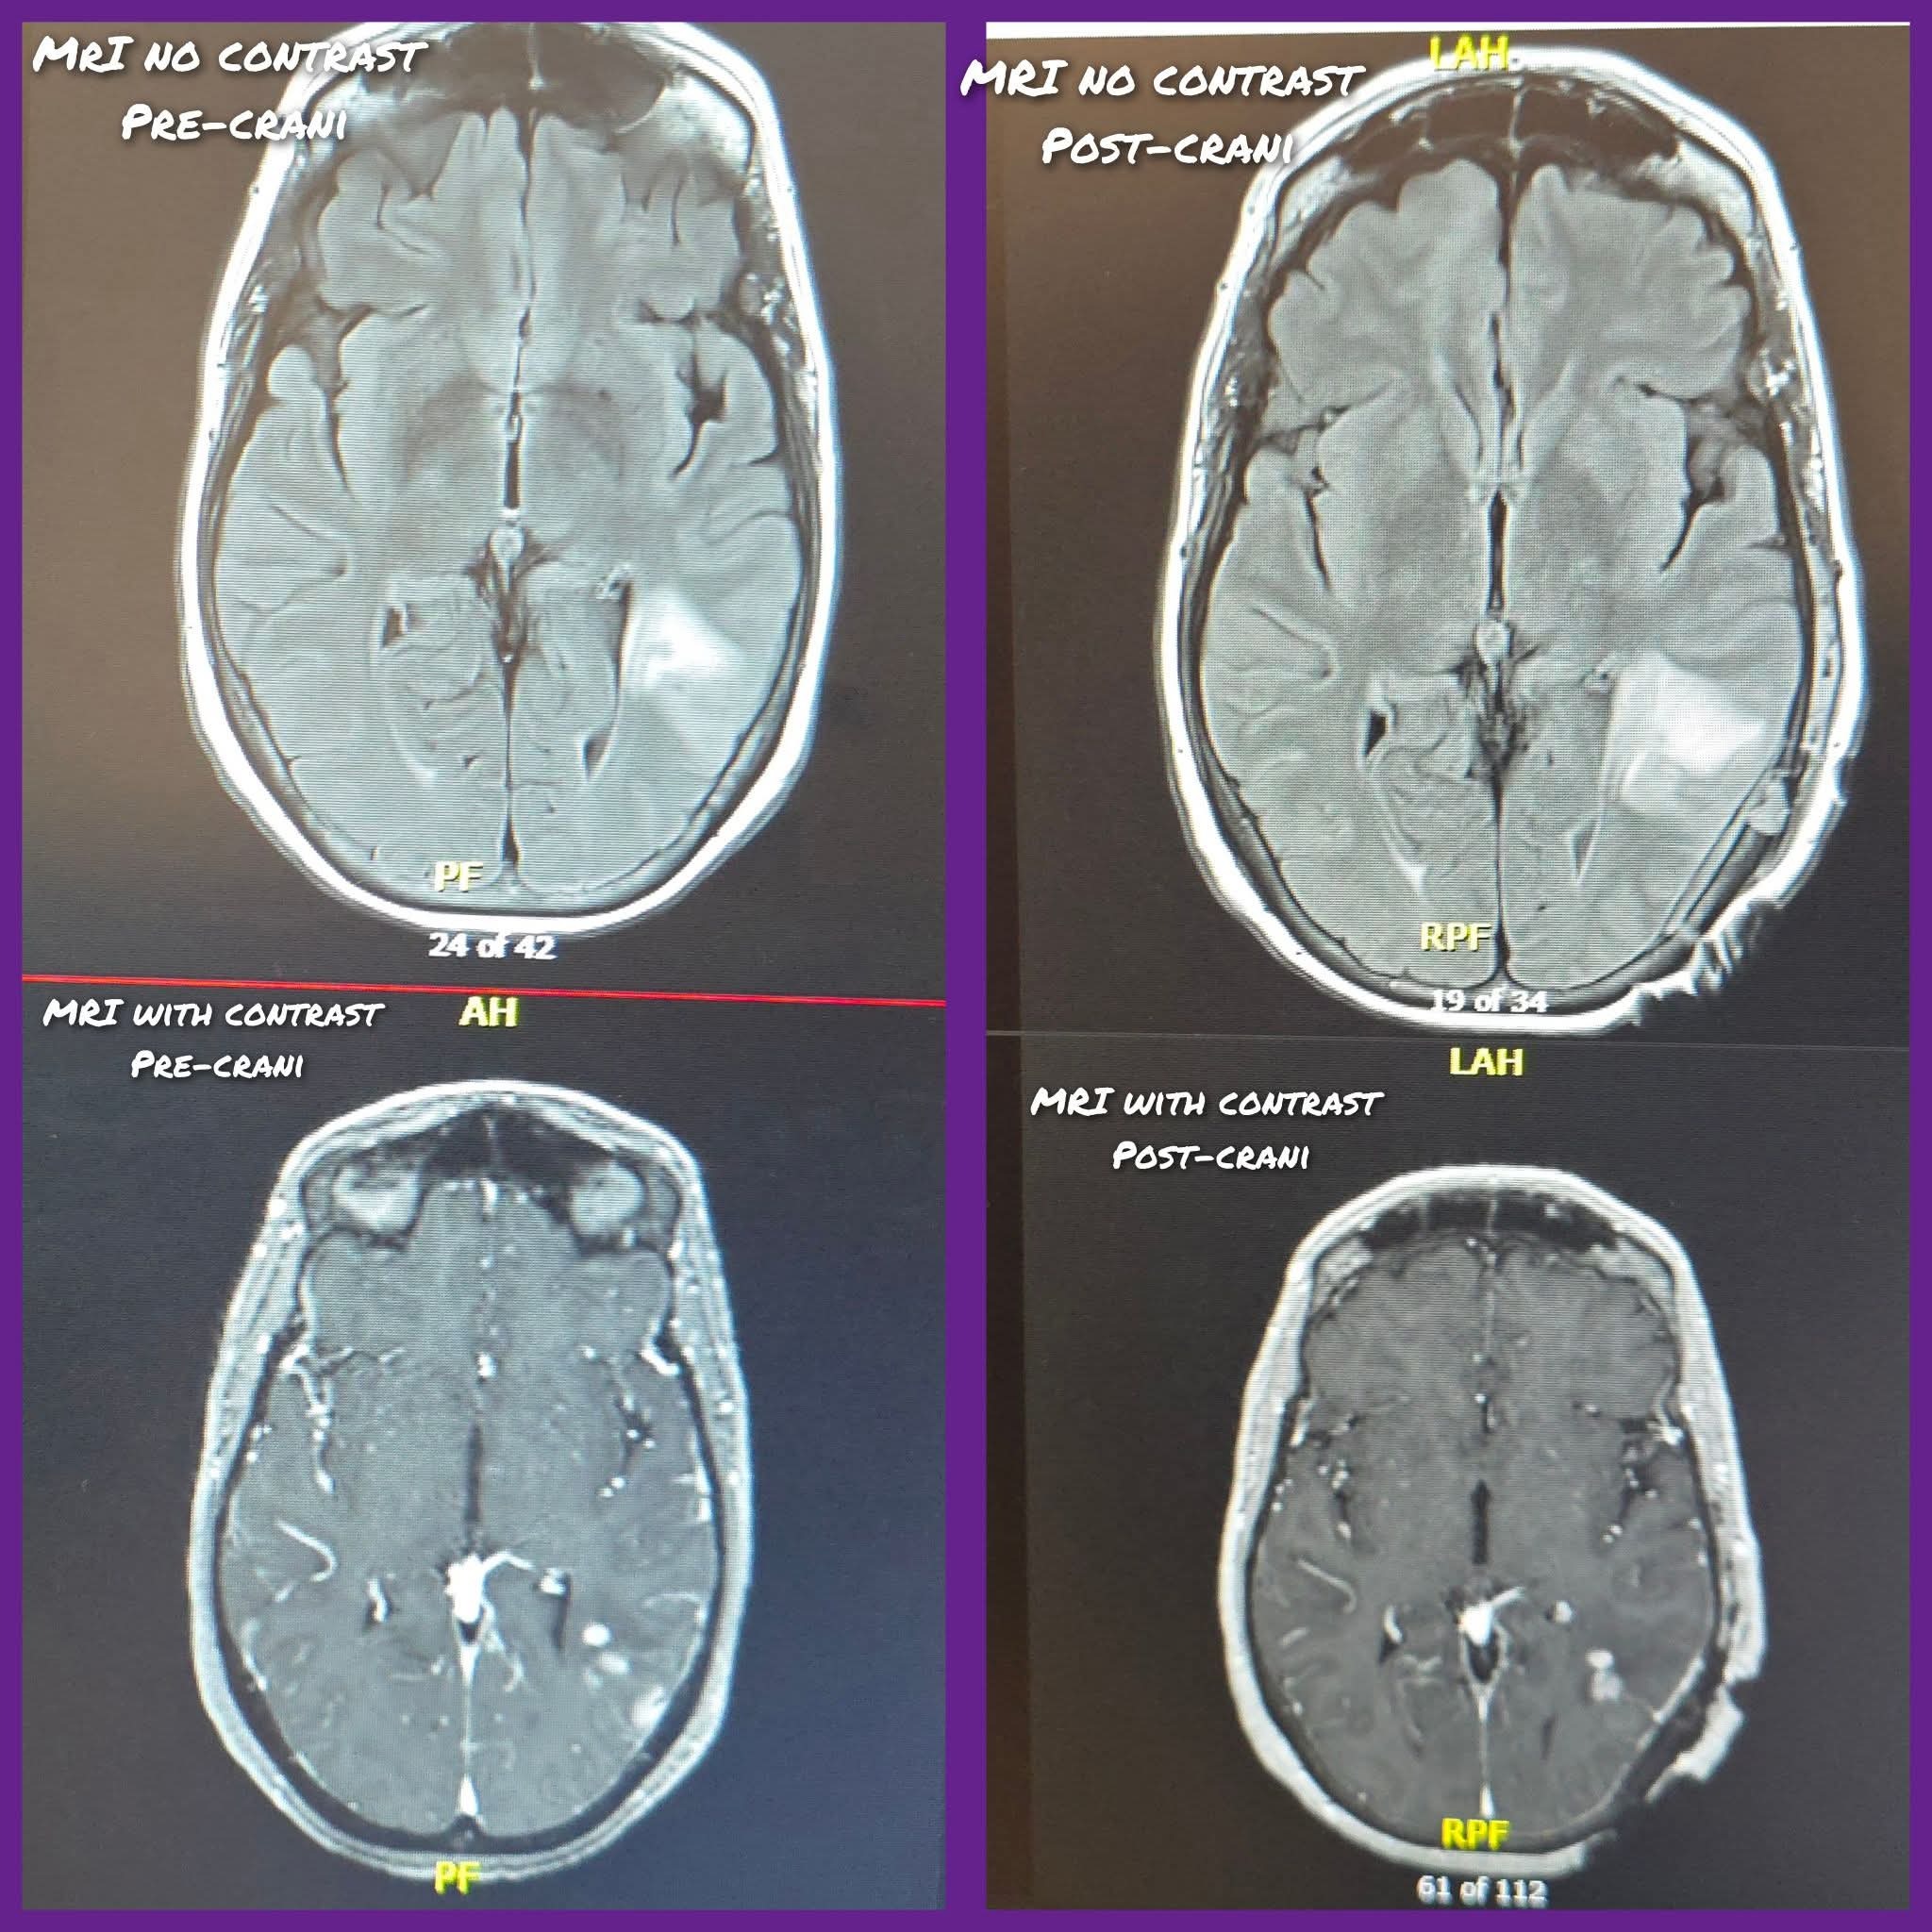

The end of November 2025 we took her up to the er thinking she was having a stroke only to find out it was a brain tumor, glioblastoma. She's been a trooper through her treatment so far but with not being allowed to work for at least a year medical bills, co-pays, and regular cost of living and normal bills that don't stop coming.